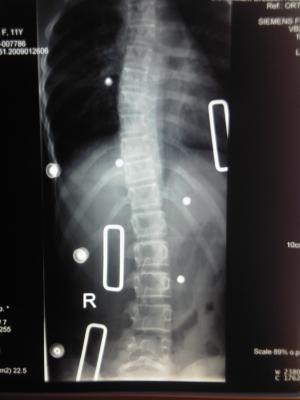

heut waren wir in dresden zum 1. röntgen.

der orthopäde war mit dem röntgenergebnis sehr zufrieden.

es wurden dann nur noch die druckpolster etwas verstärkt um eine noch bessere korrektur zu erreichen.

unsere tochter trägt ihr korsett nun seit dez 2008 regelmäßig ca. 23 std am tag.

hier nun die röntgen-ergebnisse:

geröntgt im Nachtkorestt liegend Mai 2009 - thorakal 17 Grad -  lumbal 11 Grad

Nachtk-rö.jpg (12.61 KiB) 10029 mal betrachtet

geröntgt im Tagkorsett stehend Mai 2009 - thorakal 22 Grad - lumbal 12 Grad

Tagk-rö.jpg (9.86 KiB) 10029 mal betrachtet